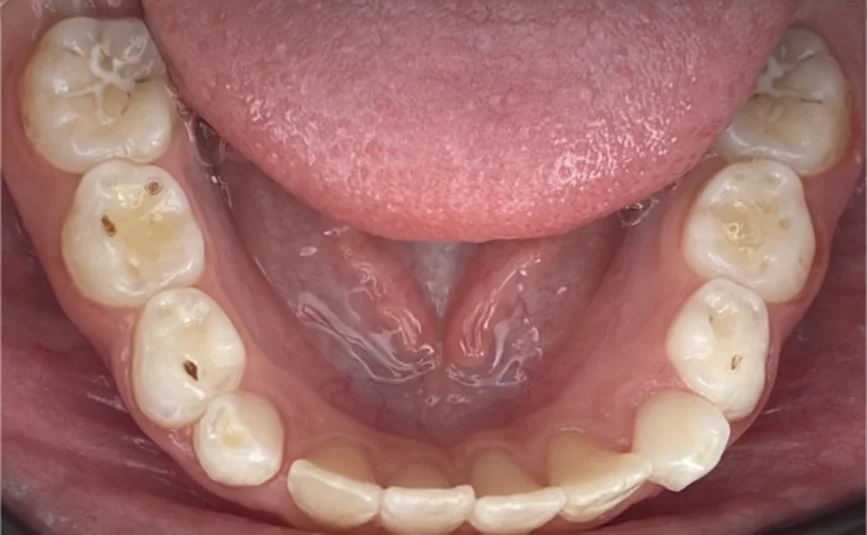

Пациентката идва на първо посещение още когато е на 6- годишна възраст, наблюдава се пробив на централни долни резци зад млечните резци. Направена е екстракция на млечни резци 81 и 71.

След една година започва лечението с алайнери. Следва интраорален скенер, анализ на рентгенографии, изработка на алайнери, поставяне на атачмънти , контролни прегледи и накрая сваляне на атачмънти.

Клинични резултати:

Хармонични зъби дъги с достатъчно място за пробива на постоянните зъби.

Осигуряване на възможност за правилен растеж и съотношение на двете челюсти.